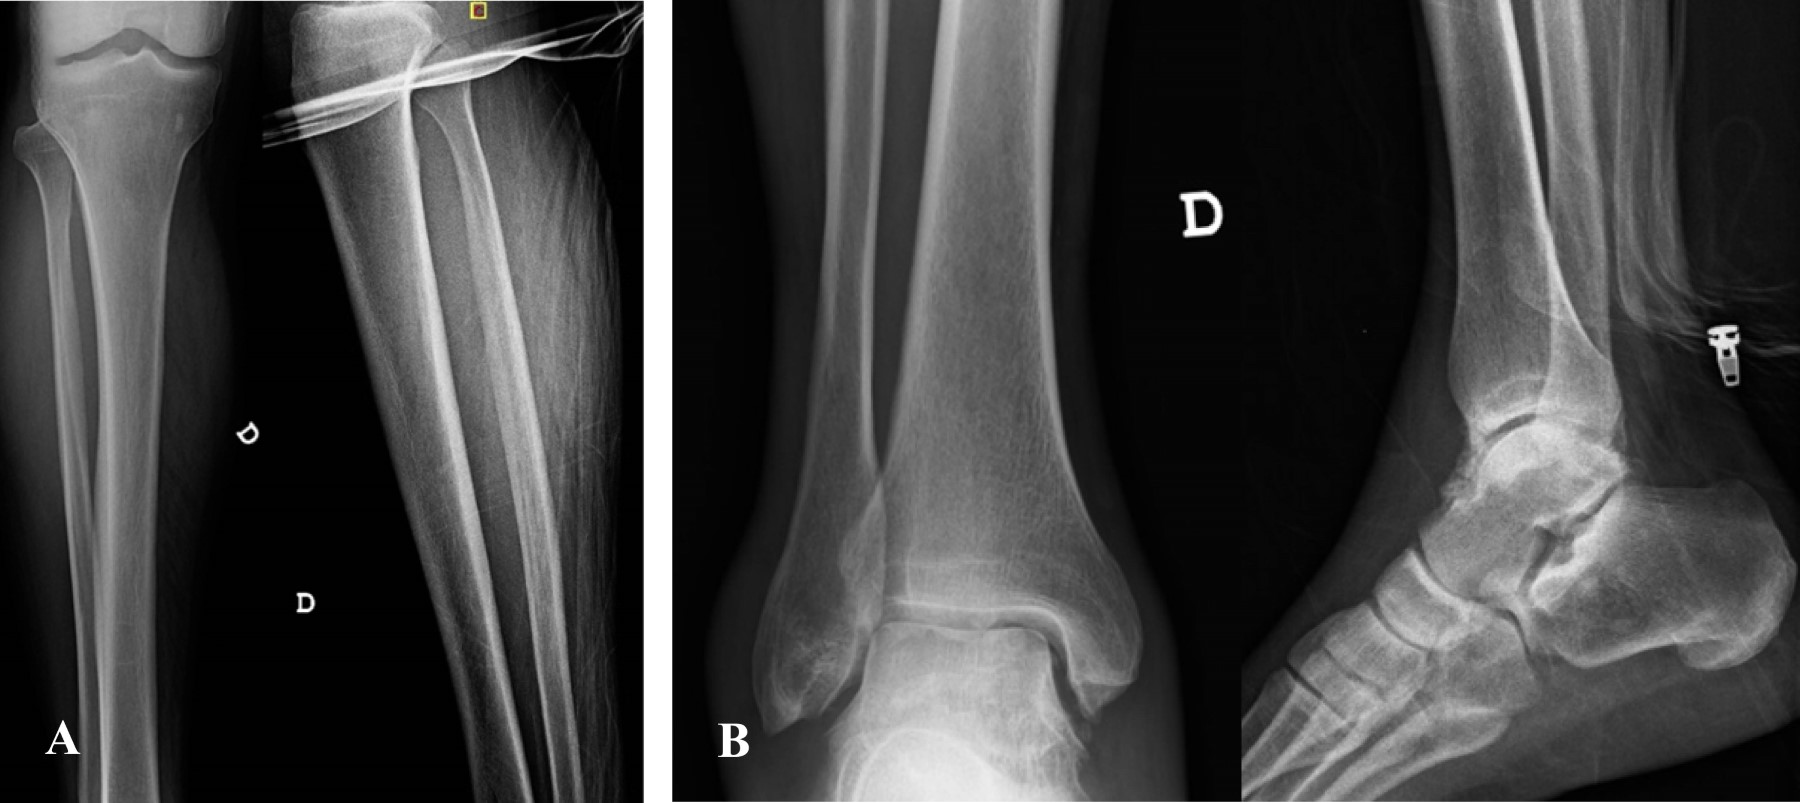

Figure 1

Figure 2

Figure 3

Figure 4

Figure 5